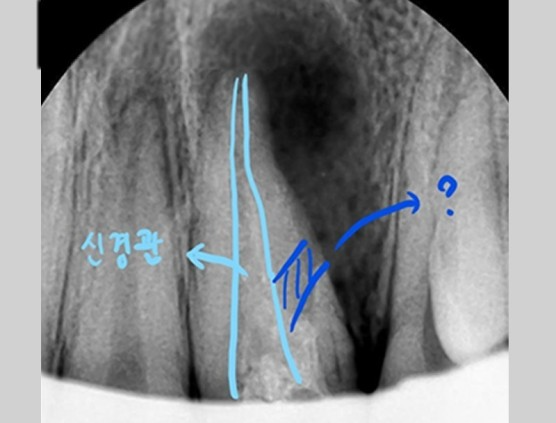

[신경관의 위치와 치아 천공의 위치]

하늘색의 신경관이 실제로 신경치료가 되어야하는 부분입니다.

하지만 파란색의 구멍을 막게 되면 좋아지리라 생각되었습니다.